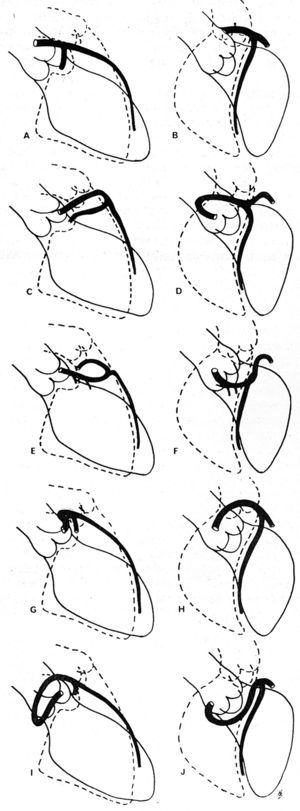

In 1985, Ishikawa et al,56 followed by Serota et al in 1990,57 proposed a series of coronary arteriographic criteria intended to define the relationship, along the initial course, between the anomalous vessel and the aorta and the pulmonary artery (Figure 11). These authors attempted to identify the different courses on the basis of the orientation of the "loop" formed by the anomalous coronary artery with the rest of the coronary tree56 or by applying the concept of the "dot" (visualization of the contrast column of the CAA which, because of the turn it makes, adopts the morphology of a dot57).

Figure 11. Illustrations of coronary angiographyc images of the left anterior descending and proximal circumflex coronary arteries in right anterior oblique projection (A, C, E, G, I) and in left anterior oblique projection (B, D, F, H, J), showing the different possible initial courses of a left coronary artery originating in right sinus of Valsalva. A and B represent a normal coronary artery; C and D show anterocranial "loop," described in the anterior course; E and F: anterocaudal "loop," septal course; G and H: posterocraneal "loop," interarterial course; I and J: posterocaudal "loop," retroaortic course. Taken from Ishikawa et al.56